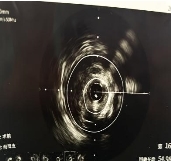

技术亮点:血管内超声,给医生装上一双“透视眼”

术中,刘主任带领团队将一个微型超声探头送入患者冠状动脉血管内。这个探头就像一台“内窥摄像机”,能够实时、高清、立体地呈现血管壁的内部结构——斑块分布在哪、血管真实直径多少、管腔面积多大、病变边界到哪里,全部一目了然。

依托这一精准的可视化导航,主刀医生像拿着高清地图开车一样,确定病变范围、测量血管参数,制定个体化手术方案。最终,支架被精准植入,完美覆盖病变部位,成功开通了闭塞、狭窄的心脏血管,恢复心脏正常供血。手术全程顺利,术中术后无任何并发症。术后复查显示:患者心脏血流通畅,心肌供血恢复正常,原本的不适症状彻底消失。